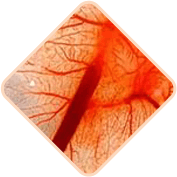

Fragilidad en los vasos

sanguíneos

del área rectal

Los vasos sanguíneos en las hemorroides pueden ser más sensibles y en algunos casos presentar sangrado. La intensidad puede variar y es importante buscar orientación profesional cuando sea necesario.